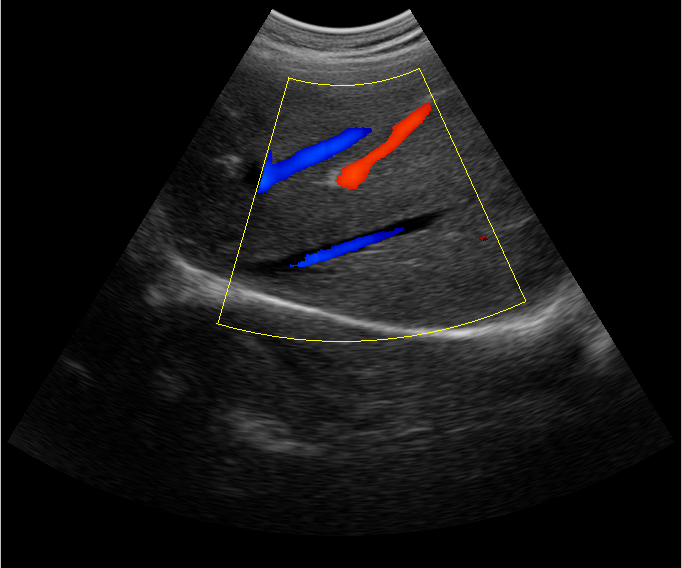

B超檢查主要是檢測肝臟的外形、大小、膽囊、門靜脈、回聲粗線等問題。由于乙肝病毒造成肝細胞破損嚴重,肝細胞出現問題,發生異常外形就會改變,通過B超檢查就能很清楚的檢查出肝臟受損的程度,以及肝臟的大小是否改變,肝臟是否發展為肝纖維化、肝硬化等。還可以檢查門靜脈主干內徑是否增寬等情況。

肝臟B超還可以通過肝臟的門靜脈、回聲粗線、膽囊等指標來診斷病情。由于肝炎病毒長期侵害會造成肝細胞破損嚴重,肝細胞出現異常,肝臟發生異常時外形就會改變。通過肝臟B超檢查就能很清楚地看出肝臟的受損程度,以及肝臟的大小、形態、回聲等是否正常。有利于肝臟的疾病的正確診斷。